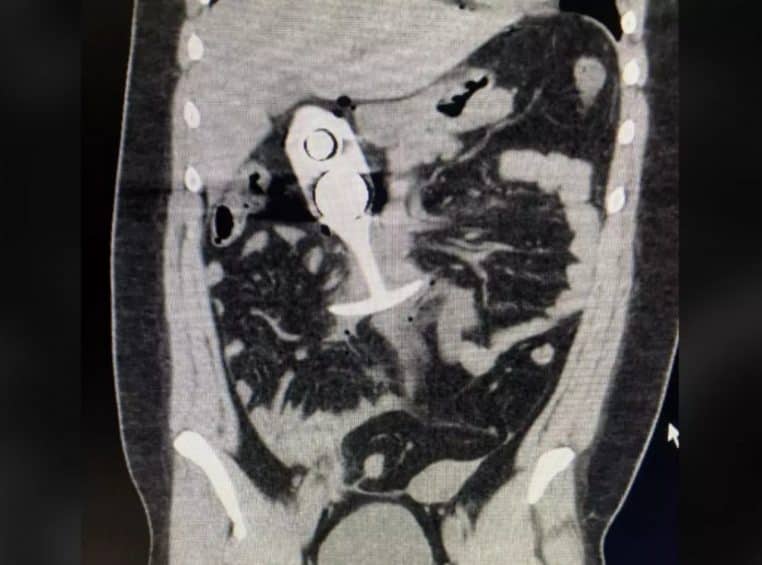

Selon Unilad, les aimants IRM seraient 100 000 fois plus puissants que le champ magnétique terrestre. En ne retirant pas le plug, la patiente s’est donc mise en danger. Lorsque l’IRM débute, la bille en métal qui se trouve à l’intérieur est attirée par les aimants IRM, et s’enfonce dans le corps de la patiente, qui préférera désormais une autre méthode pour ses plaisirs intimes.

Elle ne met d’ailleurs pas longtemps à sentir la douleur et se met à hurler. Le jouet s’est alors enfoncé dans son anus. Sur les réseaux sociaux, une image du jouet a circulé en relatant l’histoire de la femme en indiquant : « Ne portez jamais de plug anal à votre rendez-vous IRM » . Cependant, il semblerait que l’histoire ne soit pas totalement vraie. Très peu de sources existent pour corroborer cette histoire. Mais cela reste quand même un bon conseil à donner aux patients qui voudraient s’y risquer.